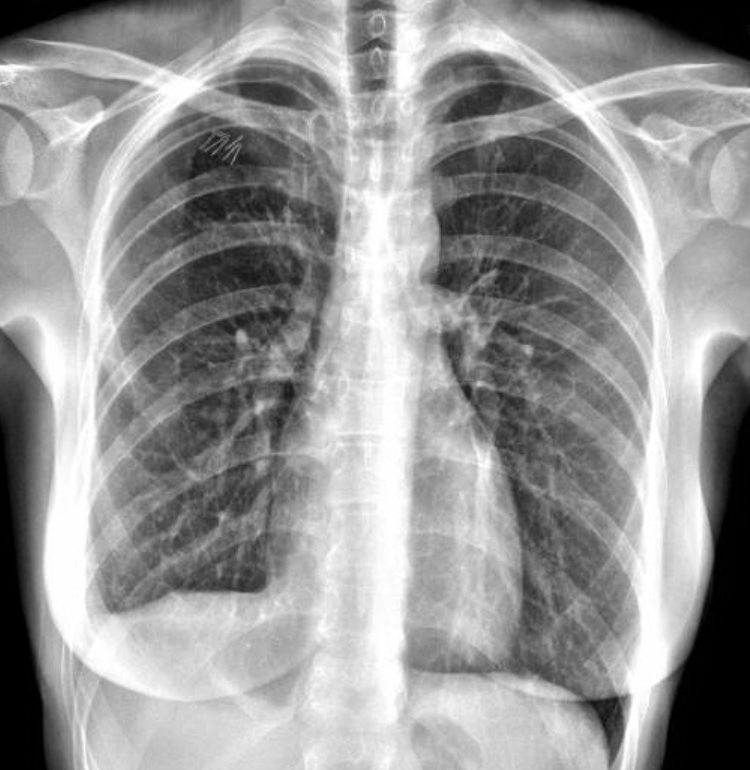

Figure 2. The patient’s 14 month postoperative chest x-ray showing no recurrence of her pneumothorax.

The patient had an uncomplicated hospital course and was discharged on postoperative day three after her chest tubes were removed. Lupron was administered within one week of discharge. She remains on Lupron Depot intramuscular shots for one year postoperation to reduce the chance of recurrent catamenial pneumothorax. She has been without recurrent pneumothorax as seen in the chest x-ray in Figure 2 at her last follow-up 14 months after surgery. Note the diaphragm patch in place on the right hemidiaphragm.